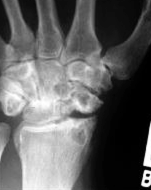

What is seen in SLAC stage 1 on xray

PA radiograph